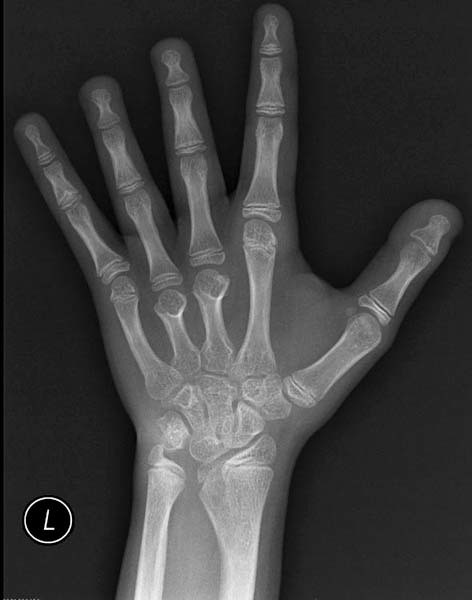

- деформация ушей, локтевых суставов, укорочение пястных костей;

- рентгенографическое исследование кистей, позвоночника, локтевых суставов для выявления их деформации и плотности костной ткани;

Укорочение кисти за счет костей ладони — характерный признак заболевания - ультразвуковое исследование почек для выявления аномалий развития;

Более редкими признаками в данном случае являются птоз, очень низкая линия роста волос на шее сзади, большое количество пигментных невусов, очень короткие четвертые пястная и плюсневая кости, особая форма подушечек пальцев – они выступают и имеют завитки на кончиках пальцев. Также может проявляться гипоплазия ногтей и вальгусное отклонение в локтевом суставе.

- рентгенография кистей и костей стоп.

Имеют место аномалии

развития скелета. В 60-70% — деформации

локтевых суставов, аномалии в строении

кистей рук, вальгусное положение коленных

суставов (Х-образное), деформация грудины

Патогенез низкорослости долгое время оставался загадкой для ученых, и лишь в середине XX в. удалось установить, что причина остановки роста кроется в мутации SHOX-гена (short stature homeobox gene). Трансформациями указанного гена определены и различные деформации скелета у больных СШТ (вальгусные явления, «готическое» небо, микрогнатия).

Внешний вид больных достаточно характерен: низкий рост (как правило, не превышает 140 см), часто избыточная масса тела, дисплазия суставов (О-образное искривление рук, Х-образное искривление ног), сколиоз, бочкообразная или плоская грудная клетка, высокое готическое небо, крыловидные складки кожи по бокам укороченной шеи (птеригиум-синдром), лицо сфинкса, микрогнатия, лимфостаз (лимфатический отек кистей и стоп).